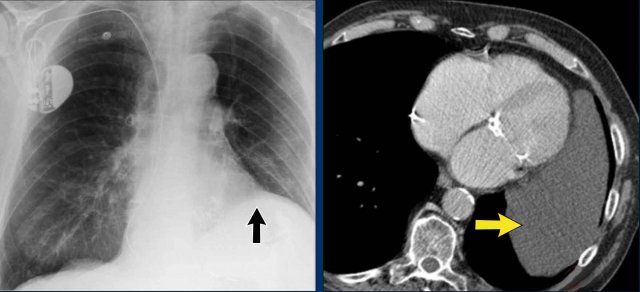

Cardiac and Pericardial Calcifications

- Coronary artery calcifications (indicative of atherosclerosis).

- Valvular calcifications (commonly involving the aortic and mitral valves).

- Pericardial Calcification are less common and may indicate chronic pericardial disease, particularly constrictive pericarditis. Appears as linear or curvilinear calcifications along the pericardial contour.

Here we see pericardial calcifications which can be associated with constrictive pericarditis.

Myocardial Calcification vs. Pericardial Calcification:

- Myocardial infarction-related calcification can resemble pericardial calcification.

- Distinction: Myocardial calcifications follow the contour of the left ventricle and are located within the myocardium, not along the pericardium.

In this case there are calcifications that look like pericardial calcifications on the chest X-ray, but these are myocardial calcifications in an infarcted area of the left ventricle.

Notice that they follow the contour of the left ventricle.